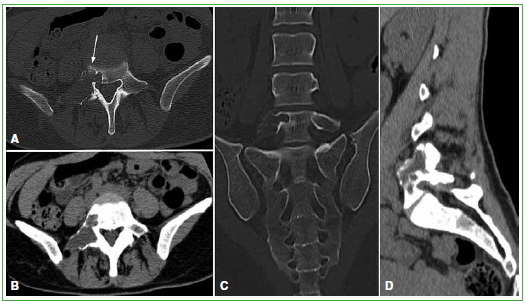

La displasia fibrosa es una lesión ósea benigna caracterizada por el desarrollo anormal del tejido fibroso de disposición arremolinada, con trabéculas de hueso inmaduro no laminar. Se distinguen dos formas: monostótica y poliostótica. El compromiso de columna vertebral se asocia, con más frecuencia, a la variedad poliostótica; la forma monostótica es infrecuente. Presentamos a una mujer de 46 años que consultó por lumbocruralgia derecha de dos meses de evolución, con diagnóstico definitivo de displasia fibrosa de columna lumbar. Los estudios por imágenes mostraron una lesión monostótica lítico-quística con tabiques internos localizada en el arco posterior de la quinta vértebra lumbar. Sus características en los estudios por imágenes sugirieron un quiste óseo aneurismático, mientras que la anatomía patológica fue reveladora frente al diagnóstico final de displasia fibrosa. Los síntomas menores y la ausencia de complicaciones llevaron a indicar un tratamiento conservador. Si bien el compromiso de columna lumbar por displasia fibrosa monostótica es infrecuente, debería considerarse entre los diagnósticos diferenciales de una lesión lítica solitaria en dicha localización. No obstante, no se descarta mediante histopatología que pueda tratarse de un caso de coexistencia de displasia fibrosa y quiste óseo aneurismático o que la displasia fibrosa se haya desarrollado sobre un quiste óseo aneurismático.Descargas